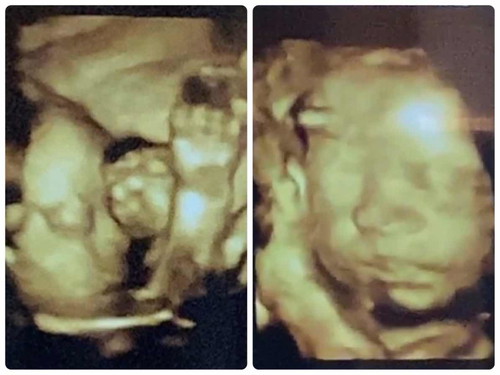

กำหนด 11 ต.ค. แม่น้ำหนักขึ้นมา 9 โล ตอนซาวด์ 28w ลูก 1,200 กรัมค่ะ